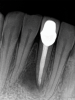

Just as systemic conditions and patient habits impact outcomes after NSRCT, the local dental environment and dental disease states also impact outcomes (Figure 1 through Figure 5). In the Toronto study evaluating 4- to 6-year outcomes following NSRCT, the presence of a periapical radiolucency emerged as a key prognostic factor, substantially reducing the success rate by a factor of four.12 Single-rooted teeth experienced better outcomes compared to multirooted teeth in the presence of periapical lesions.1 Teeth diagnosed preoperatively with irreversible pulpitis or necrosis, in the absence of AP, showed a more favorable prognosis compared to those with preoperative AP.2

Fig 2. NSRCT can have high success, even with risk factors like periapical pathology associated, as depicted in this case presentation. Fig 1: Preoperative periapical radiograph showing AP. Fig 2: Preoperative CBCT. Fig 3: Immediate postoperative periapical radiograph. Fig 4: Three-month follow-up CBCT showing reduction of periapical radiolucency. Fig 5: One-year follow-up periapical radiograph showing resolution of periapical radiolucency.

Figure 2

Fig 1 through Fig 5. NSRCT can have high success, even with risk factors like periapical pathology associated, as depicted in this case presentation. Fig 1: Preoperative periapical radiograph showing AP. Fig 2: Preoperative CBCT. Fig 3: Immediate postoperative periapical radiograph. Fig 4: Three-month follow-up CBCT showing reduction of periapical radiolucency. Fig 5: One-year follow-up periapical radiograph showing resolution of periapical radiolucency.